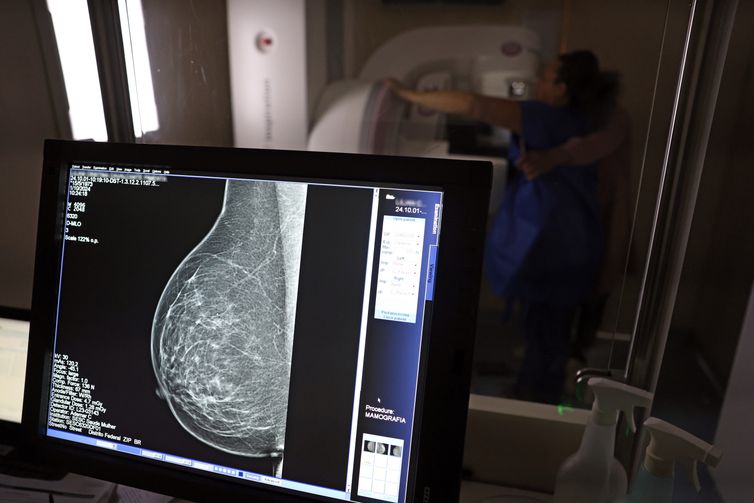

Câncer de mama é uma das doenças que mais afetam mulheres no Brasil, impactando não apenas a saúde física e emocional, mas também a capacidade de trabalho e a segurança financeira das pacientes.

No Outubro Rosa, o Instituto Nacional de Câncer (Inca) estimou 73.610 novos casos este ano no país. É o câncer que mais mata mulheres no Brasil. As mulheres em tratamento pela doença têm o direito de receber o auxílio-doença ou o benefício de prestação continuada.

FONTE/CRÉDITOS (IMAGEM DE CAPA): © José Cruz/Agência Brasil